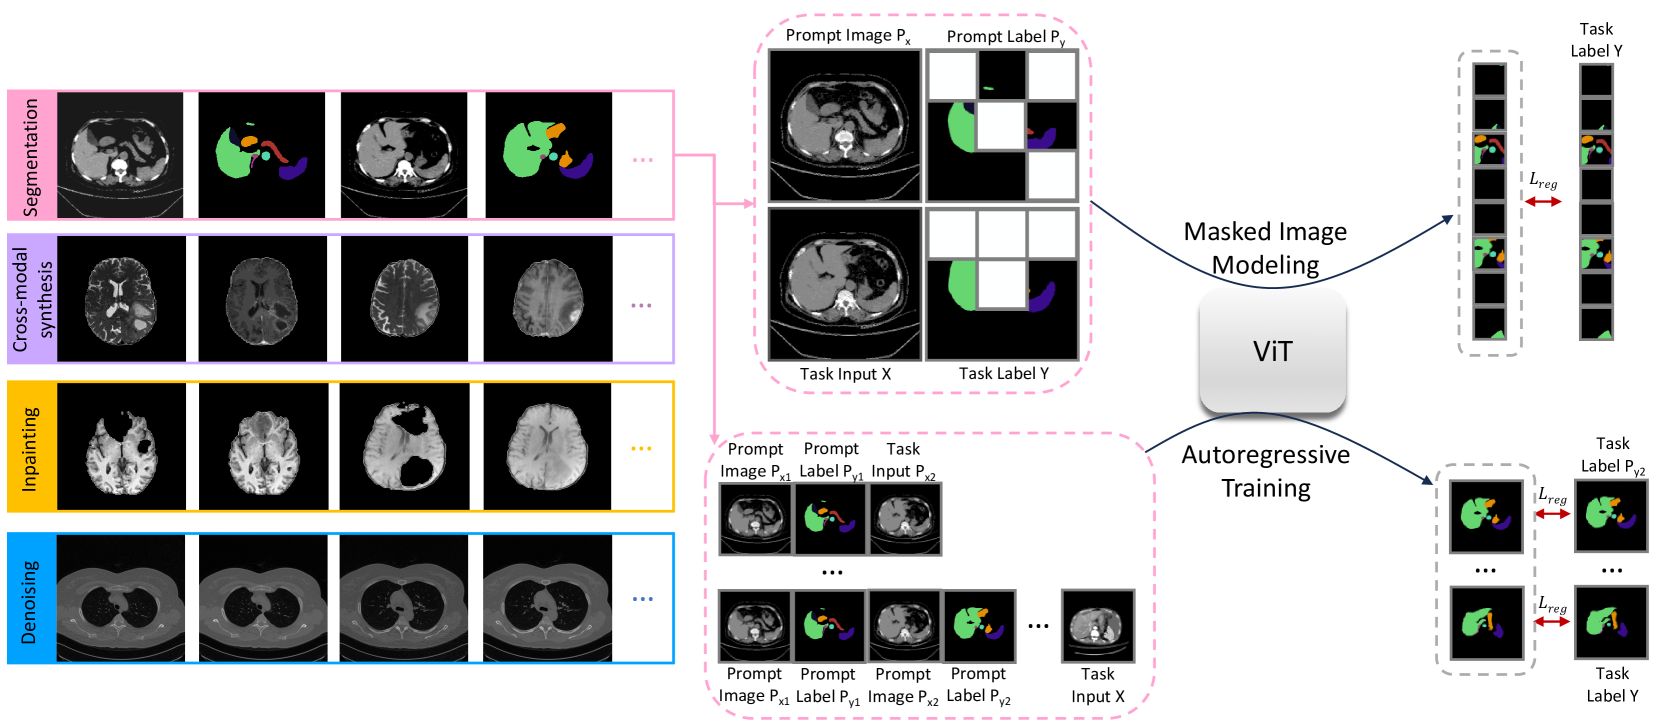

This study presents Medical Vision Generalist (MVG), the first foundation model capable of handling various medical imaging tasks—such as cross-modal synthesis, image segmentation, denoising, and inpainting—within a unified image-to-image generation framework. Specifically, MVG employs an in-context generation strategy that standardizes the handling of inputs and outputs as images. By treating these tasks as an image generation process conditioned on prompt image-label pairs and input images, this approach enables a flexible unification of various tasks, even those spanning different modalities and datasets. To capitalize on both local and global context, we design a hybrid method combining masked image modeling with autoregressive training for conditional image generation. This hybrid approach yields the most robust performance across all involved medical imaging tasks. To rigorously evaluate MVG’s capabilities, we curated the first comprehensive generalist medical vision benchmark, comprising 13 datasets and spanning four imaging modalities (CT, MRI, X-ray, and micro-ultrasound). Our results consistently establish MVG’s superior performance, outperforming existing vision generalists, such as Painter and LVM. Furthermore, MVG exhibits strong scalability, with its performance demonstrably improving when trained on a more diverse set of tasks, and can be effectively adapted to unseen datasets with only minimal task-specific samples. The code is available at https://github.com/OliverRensu/MVG.

Motivated by the remarkable success of in-context learning in natural language processing [22, 23] and computer vision [24, 25, 26], we hereby propose Medical Vision Generalist (MVG), the first generalist model in the medical imaging domain. Specifically, MVG leverages an in-context learning framework to unify a set of medical imaging tasks, including cross-modal synthesis, denoising, segmentation, and inpainting across modalities like CT, MRI, X-ray, and Micro-ultrasound. In contrast to prior task- and data-specific medical AI models, MVG offers adaptability to new data with minimal labeled samples, eliminating the need for retraining. To achieve this, MVG first standardizes the input/output space using in-context coloring, which maps various tasks into a single-channel coloring scheme. This removes the need for task-specific heads, thus regulating the model to learn exclusively from prompts. Subsequently, tasks are unified through conditional image generation, where MVG generates output conditioned on both the task prompt and a sample image.

To capture both local and global context, we devise a hybrid strategy that combines masked image modeling and autoregressive training for conditional image generation. The former involves concatenating prompt images, labels, task inputs, and labels, followed by random masking; the latter constructs prompt image-label pairs, task inputs, and labels as long visual sentences. During inference, MVG conditions predictions on the prompts selected from locations closely matching the task images, ensuring contextual relevance and guidance that enhances output quality and consistency.

3.3 Task Unification via Conditional Image Generation

After standardizing the input and output space for all tasks as images of identical sizes, we construct the training input, including 1) the task prompt consisting of paired prompt images and prompt labels, and 2) the task input and its associated label. We then unify various medical imaging tasks within a conditional image-to-image generation framework using the task prompt as task specification. All the tasks are unified to generate the task label based on the condition including the task image , the prompt image , and the prompt label . Specifically, we use two conditional image generation frameworks - mask image modeling [42] and autoregressive training [43].

Mask Image Modeling.

During training, we form a square image by concatenating the prompt image (upper left) with its corresponding label (upper right), as well as the task image (lower left) with its associated label (lower right), as illustrated in Figure 3(a). We perform random masking on the square image and train ViT to reconstruct the masked region [26]:

where is the mask region, is the visible region, and denotes the model parameters. However, in practice, we observed that mask image modeling yields unsatisfactory results for medical image segmentation. We hypothesize that this may be attributed to the masking strategy’s potential to compromise the preservation of global contextual information and to ignore small regions-of-interest. To ensure the efficacy on medical image segmentation, we introduce an additional auto-regressive training, which preserves the global context within individual images, as shown below.

Auto-Regressive Training.

In auto-regressive training, each image, including paired prompt images, prompt labels, task inputs, and associated labels, is treated as a single element in a sequential data structure. The model is fed with a partial sequence and trained to predict the next image in the sequence conditioning on the preceding ones.

Mathematically, let denote pairs of images and labels. The first pairs serve as the task prompt, and the model learns to predict the task output given the task input and the prompt. This process iterates through each pair in the sequence. For each iteration, auto-regressive training is conducted with supervision solely on prompt labels and the task label: